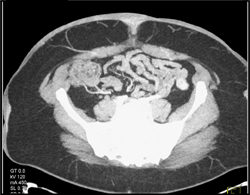

Diagnosis

Mess?? Abdominal Wall